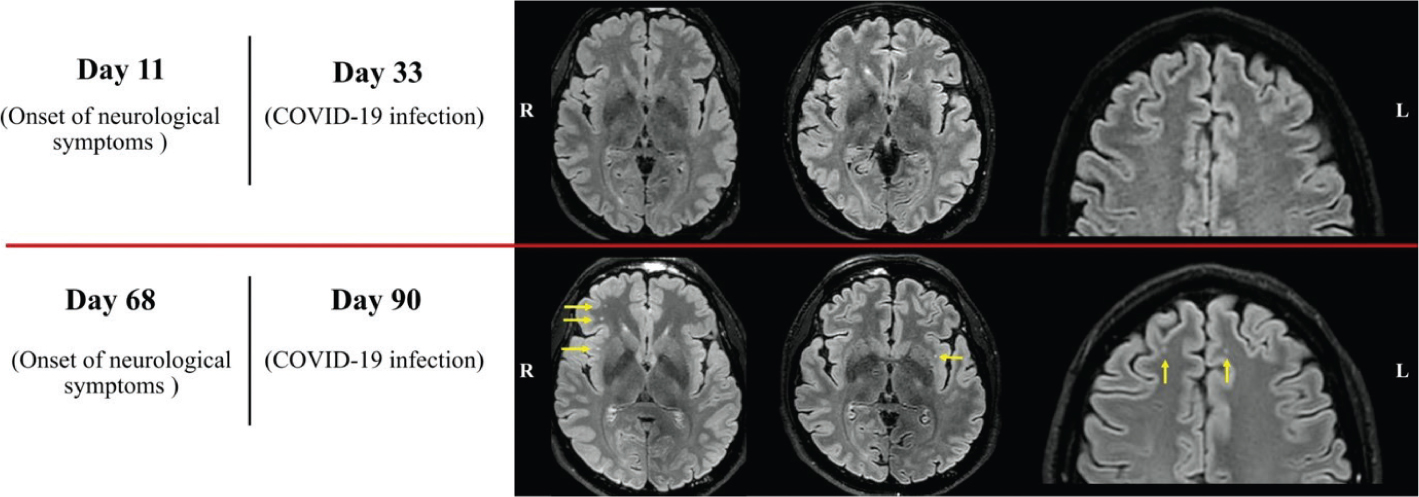

Fig 1

Figure 1. The trend in neuroradiological detection of white matter changes in our patient is summarised. FLAIR images from the second (top row) and the third (bottom row) MRI examinations. Several new subcortical white matter changes were found and are highlighted with yellow arrows. The discrepancy was not considered to be explained by the slight difference in image quality. All other sequences in all three MR examinations showed normal findings.

The first two MRI scans (day 2 and day 11 from neurological symptom onset) were negative (Figure 1, top row). When we compare the first DTI analysis (day 11) with the HC group, the right uncinate fasciculus (UF) and the cortico-spinal tract (CST) displayed focal signs of myelin changes compared with HC (high fractional anisotropy [FA], low axial diffusivity [AD] and low radial diffusivity [RD]). The right frontal aslant tract (FAT) and the right inferior fronto-occipital fasciculus (IFOF) displayed signs of axonal changes (low FA, low AD and low RD, highlighted in red in Figure 2). The other analysed white matter bundles did not show a significant difference compared with HC. In the third scan (day 68), several new, rounded subcortical white matter changes had appeared in frontal and sub-insular regions (predominantly in the right hemisphere) (Figure 1, bottom row). When the second DTI analysis (day 68) was compared with the first one and the HC group, we identified a partial regress of myelin changes in the right UF, the right CST and in the right IFOF. The right FAT showed steady focal axonal changes between investigations (at the compared AD abnormalities distribution), while the left horizontal component of the superior longitudinal fasciculus (hSLF) displayed new significant diffusion changes possibly reflecting myelin damage (low FA, high AD and high RD).